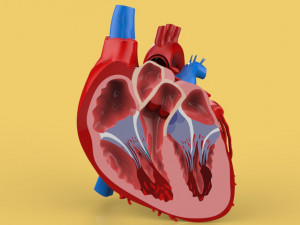

The model meshes include adult circulation versus circulation in Tetralogy of Fallot (TAF), arrow labels and text labels. The blood flow in a patient with Tetralogy of Fallot is outlined in this model. To contrast it to normal blood circulation a separate model of normal circulation is included. The Tetralogy of Fallot (OVER RIDING OF AORTA, PUL STENOSIS, VENTRICULAR SEPTAL DEFECT, RIGHT VENTRICULAR HYPERTROPHY), fossa, ligament teres , venosus, and arteriosus are duly depicted with proper labelling and blood flow directional arrows. Excellent model for teaching, demonstration and knowlegde of human body. The models include both procedural and image textures blend files separately. The texture file include diffuse, roughness and normal png and jpeg based on non overlapping UV maps.